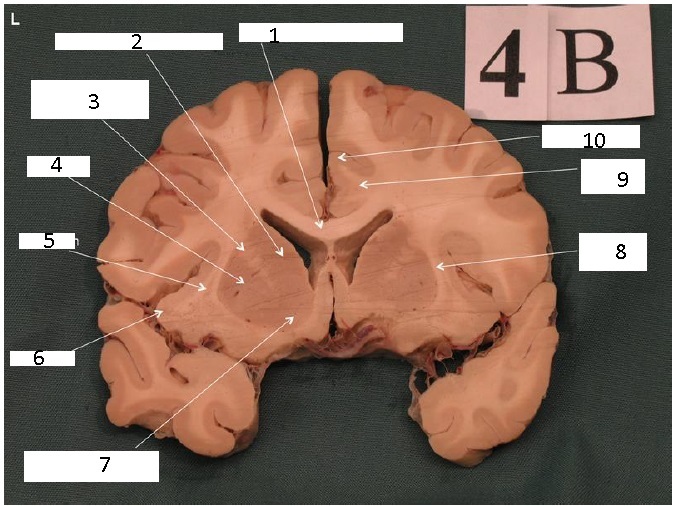

Identify 1

Body of Corpus Callosum

Identify 2

Head of Caudate Nucleus

Identify 3

Anterior Limb of the Internal Capsule

Identify 4

Putamen

Identify 5

Claustrum

Identify 6

Insula

Identify 7

Nucleus Accumbens

Identify 8

External Capsule

the lateral portion of the ‘A’ formed by the external and internal capsule

Identify 9

Cingulum

Identify 10

Cingulate Gyrus